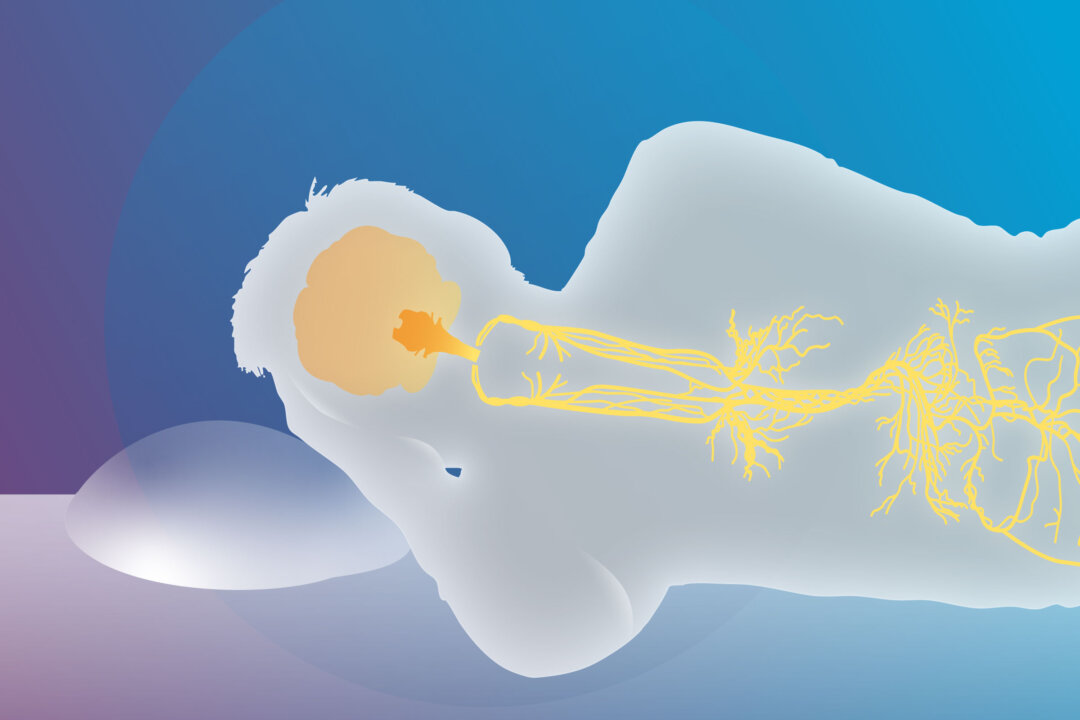

Stimulating the vagus nerve may help people with insomnia sleep better by calming the nervous system and encouraging natural sleep rhythms. Vagus nerve stimulation (VNS)—either mechanically with devices or by breathwork—is increasingly being explored as an alternative to conventional sleep treatments.

By stimulating the vagus nerve, the parasympathetic state of rest and digest is activated and sympathetic overactivity is reduced, influencing key brain areas involved in sleep–wake cycles and stress responses.